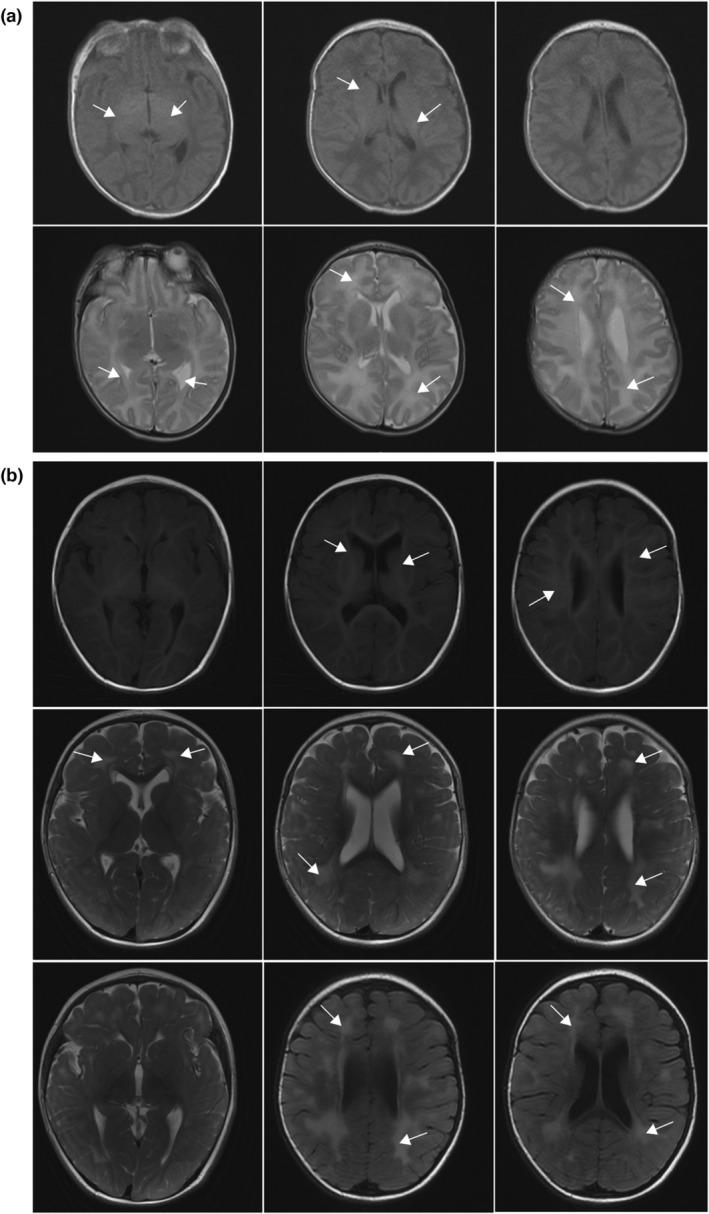

Here, we report a patient with DD, hypotonia, early atrial septal defect, and abnormal white matter signal. She presented with Shashi-Pena syndrome with a truncated variant in ASXL2 (NM_018263.6, c.2142_2152del, p.Ser714Argfs*5). She died of a digestive tract infection when she was 1 year and 6 months old.

The clinical data such as brain MRI were collect. The whole exome sequencing was performed for genetic etiology analysis.